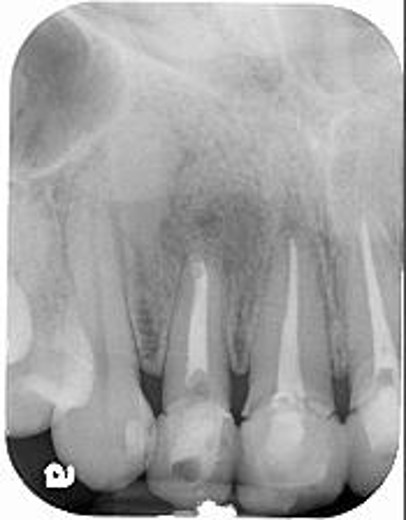

治療前,前牙病變,阻生齒等

治療前,前牙根管治療不完全

治療前,牙齦旁有黑邊

根管治療6個月後,仍有根尖病變

6個月後病變逐漸恢復

再6個月後,病變更消失